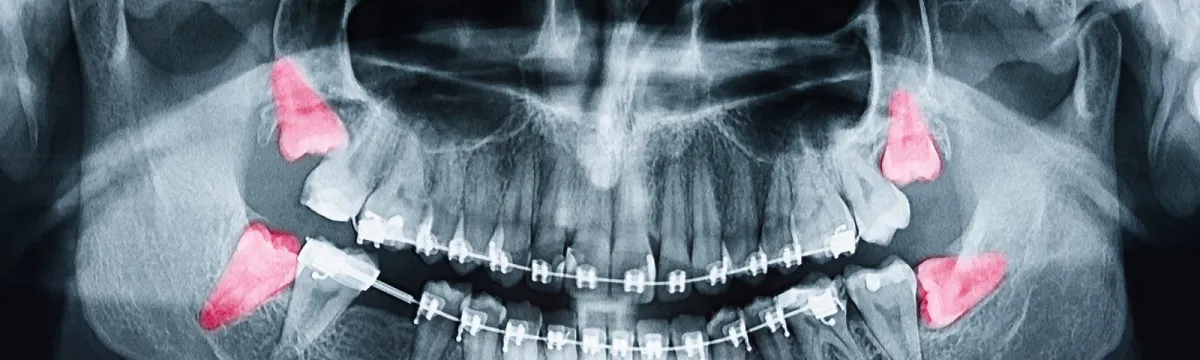

- Покраснение вокруг десны, отек. Нередко бывают случаи, когда третьи моляры прорезываются не полностью, не прорезываются вовсе. Это связано с тем, что физиологически нет условий для нормального роста крайних зубных единиц. Какое-то время никаких проблем не наблюдается. Но результат всегда неблагоприятный – болезненные ощущения, покраснения, отек, смещение зубов.

- Неправильный прикус. Еще одна причина, почему надо удалять зуб мудрости. Нестандартное расположение, рост «восьмерки» нередко приводит к формированию неправильного прикуса. Как правило, такая проблема проявляется уже во взрослом возрасте. Что усложняет ее исправление.